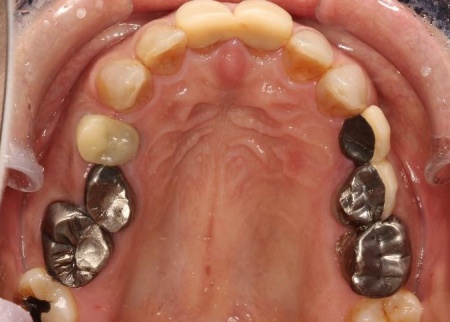

治療前

まずは、口腔内全体の矯正治療から開始します。

上顎は左上の歯が欠損していたため、左右のバランスを整える目的で、右上の歯(第1小臼歯)を抜きました。

その後、ワイヤー矯正とクローズドコイル(バネの装置)を使ったスピード矯正を行い、前歯を後方に移動させます。

下顎は残根も利用しながら、矯正用の小さなネジ「テンポラリーインプラント(インプラントアンカー)」を顎の骨に埋め込んで固定源とする方法も併用し、歯を移動させました。

上顎の前歯2本ずつと奥歯4本(左右中切歯・第2小臼歯・第1大臼歯)、下顎の奥歯7本(左第1小臼歯・左右第2小臼歯・第1大臼歯・第2大臼歯)には、見た目が自然なセラミックの被せ物「ジルコニアクラウン」を装着しました。

ジルコニアは、金属を使わないため金属アレルギーの心配が少ない点、人工ダイヤモンドと呼ばれるほどの強度をもち噛む力の強い奥歯にも適している点がメリットです。

加えて、上前歯4本(左右側切歯・犬歯)と下前歯5本(左右中切歯・側切歯・右下犬歯)は、ダイレクトクラウンによる修復を行いました。

ダイレクトクラウンとは、レジン(樹脂)を用いて直接歯の形を作り上げていく治療方法です。

歯を削る量が少ない、色や形を細かく調整しながら仕上げられる、治療後は必要に応じて微調整がしやすいなどのメリットがあります。